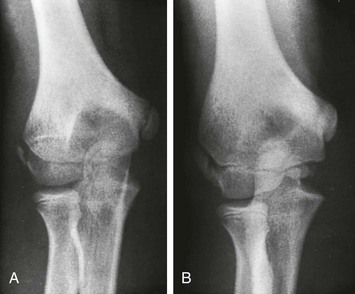

Figure 129-38 An 11-year-old boy with a normal elbow.

As a rule, the medial epicondylar ossification center (arrow) should appear before the trochlear ossification center (arrowhead). If only the trochlear ossification center is present, a medial epicondylar avulsion fracture should be suspected.